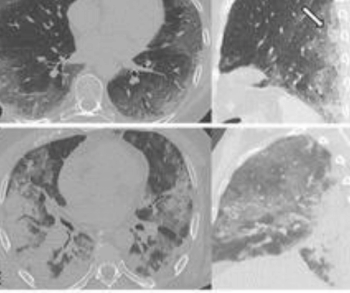

The retrospective study, which involved nearly 1,000 patients with COVID-19, found that a high initial chest radiograph severity score was an independent risk factor for intrathoracic complications.